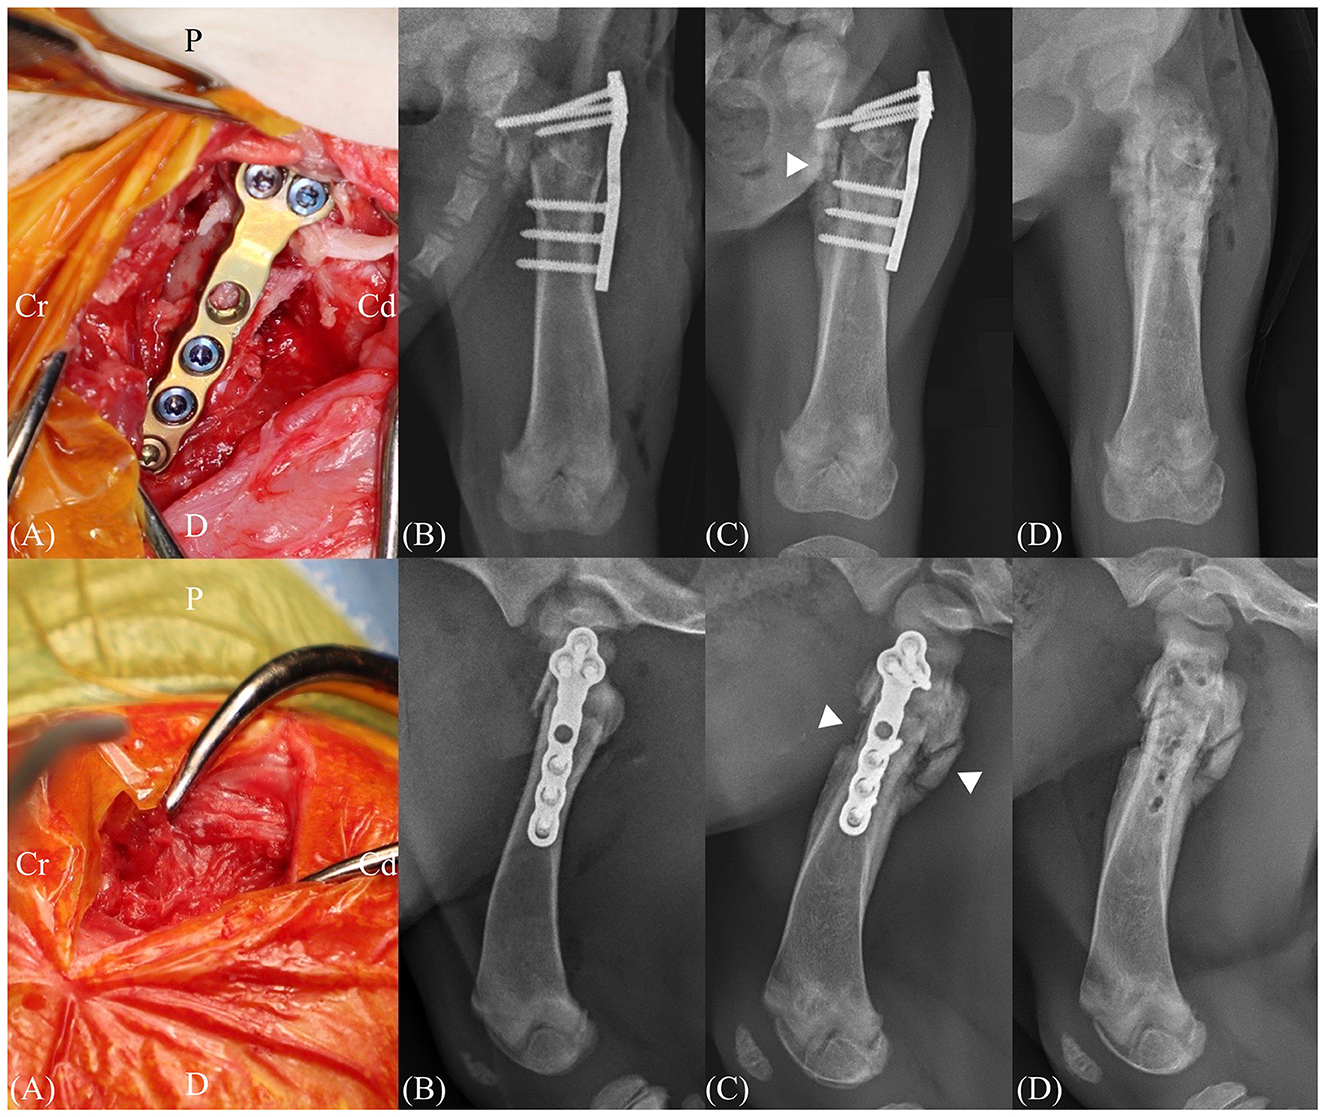

This case report describes the successful management of a subtrochanteric femoral fracture in a 2-month-old dog using temporary supratrochanteric plate fixation, performed prior to the development of the greater trochanter apophysis. A tibial plateau leveling osteotomy plate was applied to the proximolateral femur and subsequently removed following radiographic evidence of bridging callus formation. At the 21-month follow-up, the dog exhibited normal limb function, symmetrical femoral length, and appropriate development of the greater trochanter. Although a mild procurvatum deformity was noted, no clinical signs or range of motion deficits were observed. These findings support the use of temporary fixation across the trochanteric region as a feasible treatment strategy for immature subtrochanteric femoral fractures when performed prior to apophyseal development.